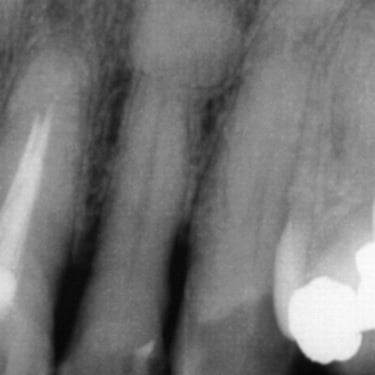

Reabsorción Interna

La reabsorción interna es la destrucción progresiva de la dentina desde el interior del diente hacia afuera, generalmente debido a un trauma o inflamación pulpar.

Los pacientes pueden notar un cambio de color en el diente.

Es necesario un tratamiento de conducto para detener el proceso y salvar el diente. Sin tratamiento, el diente puede debilitarse y fracturarse.